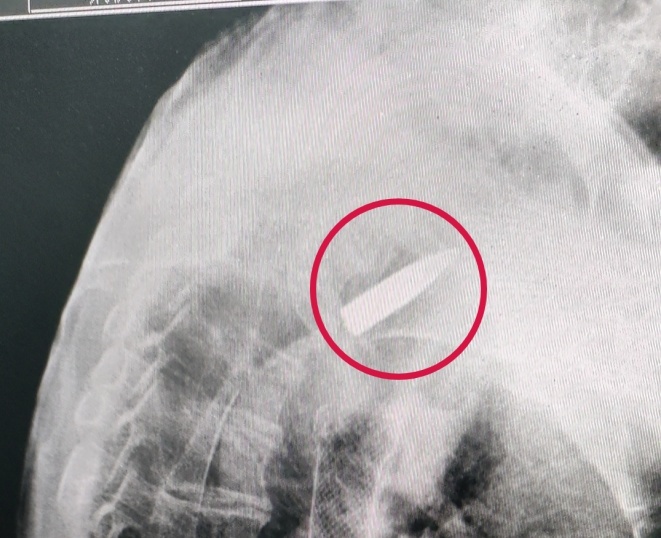

结果CT拍出来

医生们都吓了一跳

罗锦文的右肩里

竟然有一颗子弹

而这颗“长”在他身体里74年的子弹

是对那段历史的最佳见证

考虑到这枚子弹对日常生活影响不大

经医院和家属商议

决定保持原状

不进行取出